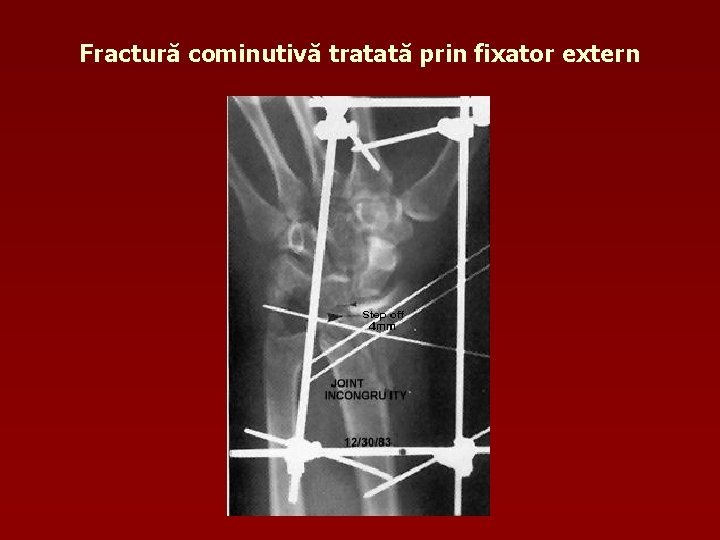

Fractură cominutivă tratată prin fixator extern